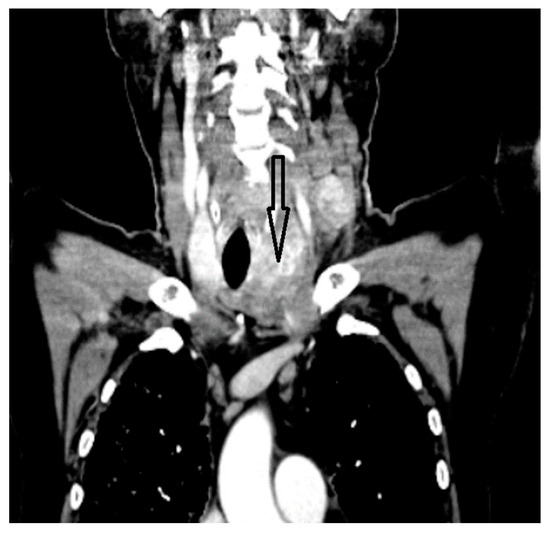

Aggressive Primary Thyroid Mucoepidermoid Carcinoma with Extensive Pulmonary Involvement

2. Case Report